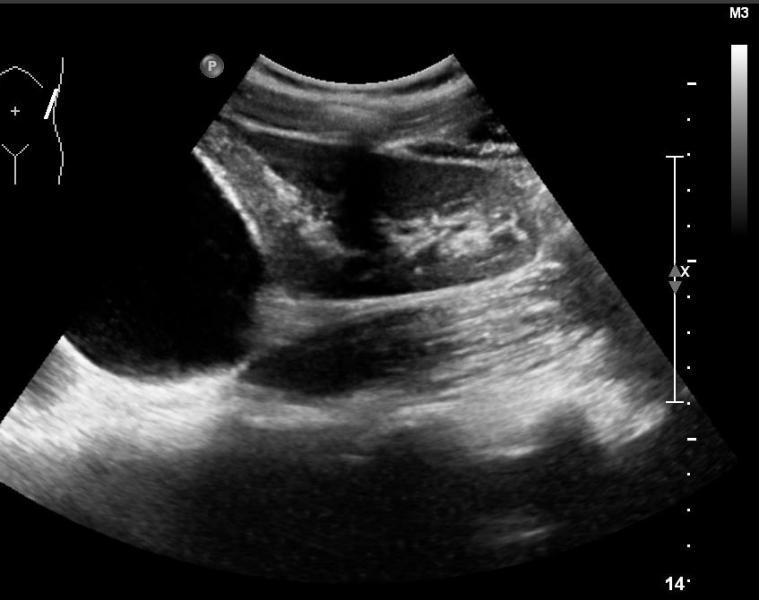

Rozpoznanie: W badaniu USG uwidoczniono wgłobienie krętniczo-kątnicze (białe strzałki).